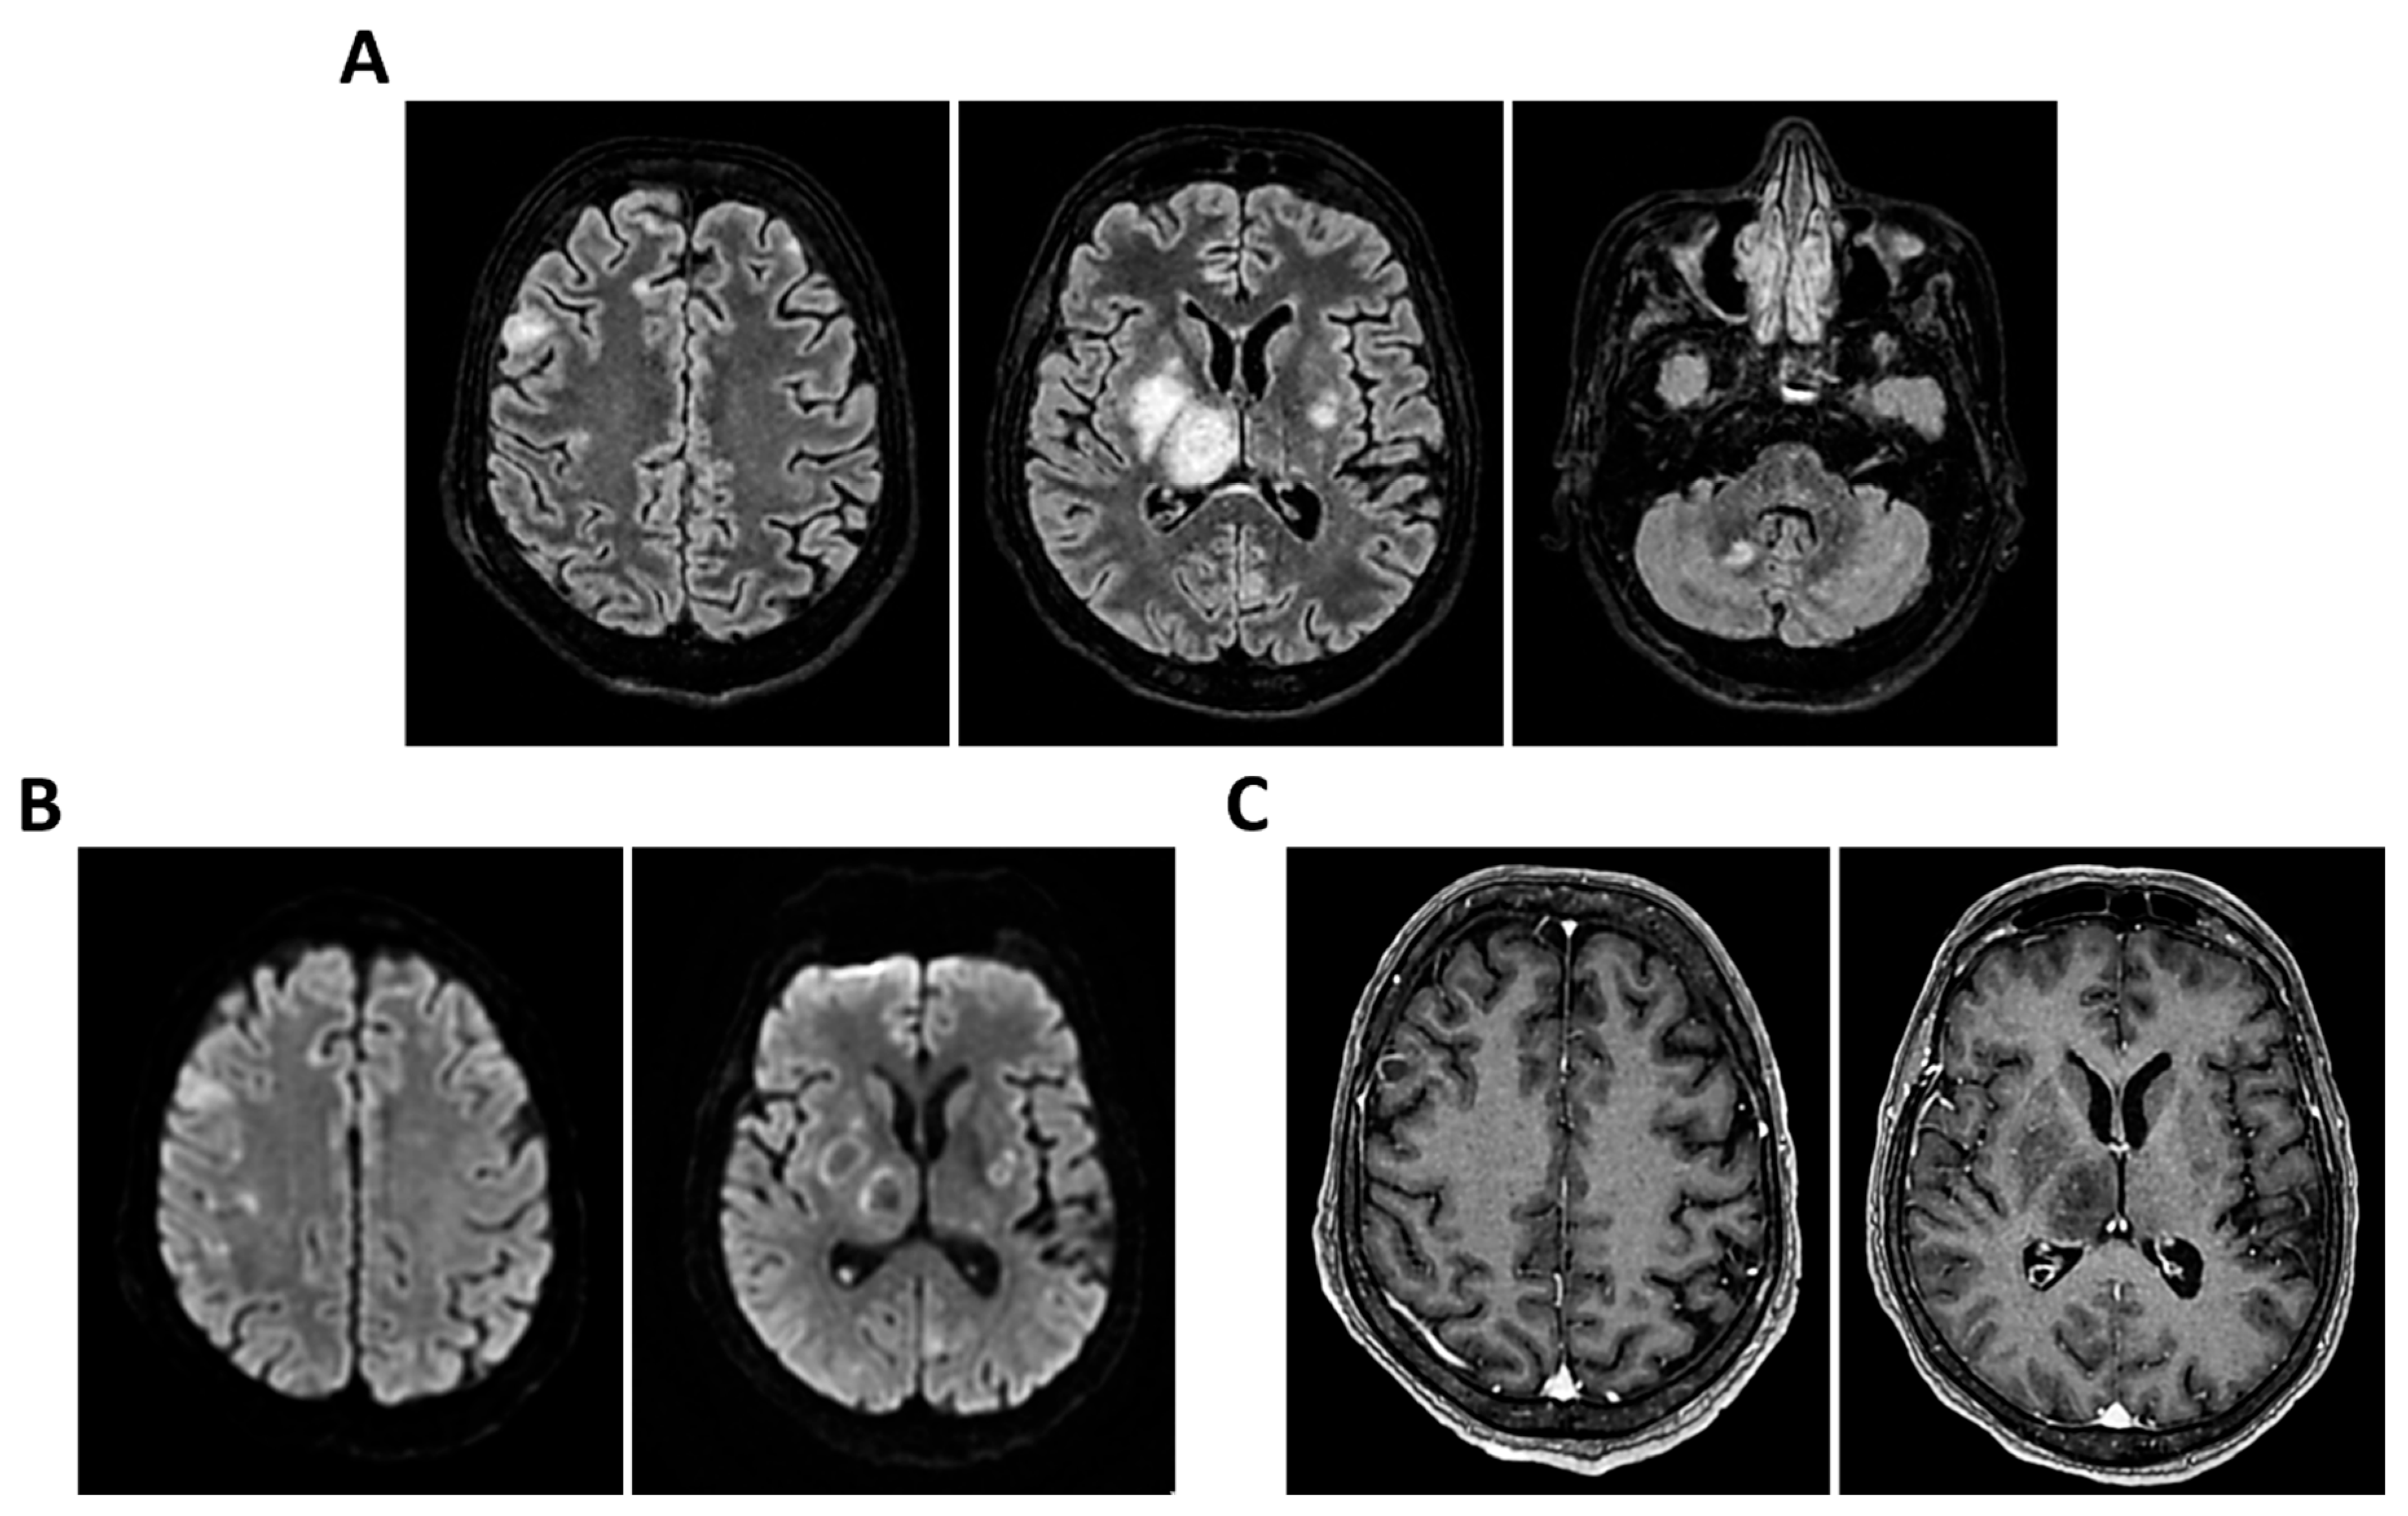

Figure 10.

MRI of patient 5 group 2. A 67-year-old woman with schizophrenia presented to the ER with lethargy and vomiting, following 10 days of fever and dry cough treated ineffectively with Medrol and Cefditoren. Brain CT showed a left temporoparietal hypodensity (sequela) and supratentorial ventricular dilation without midline shift. The lumbar puncture was positive for Listeria monocytogenes (FilmArray). Due to neurological deterioration (GCS 7), she was transferred to the ICU. On day 2, TCCD showed PI values of 1.65 (right) and 1.89 (left), indicating increased cerebral vascular resistance without clear signs of intracranial hypertension. (A) 3D axial FLAIR shows marked and diffuse atrophy of the brain tissue, more pronounced in the left hemisphere where some areas of enlargement of the cerebrospinal fluid spaces are observed, more prominent in the parietal region, and diffuse dilation of the supraventricular system, particularly in the occipital horns. (B) Perfusion study reveals minimal asymmetry in cerebral perfusion values sampled at the level of the semioval centers. Blue circles indicate the ROI used for quantitative CBF analysis.

3.2. Group 2: TCCD and Perfusion MRI with ASL

The second patient, affected by L. monocytogenes meningoencephalitis, showed bilateral elevation of PI (1.65 and 1.89) and significant CBF asymmetry (right CBF: 105 mL/100 g; left CBF: 91 mL/100 g) (Table 3 and Figure 10).

Both patients died by day 28. Notably, these two cases demonstrated a mismatch between regional perfusion and vascular impedance, consistent with cerebrovascular dysregulation and loss of autoregulation.